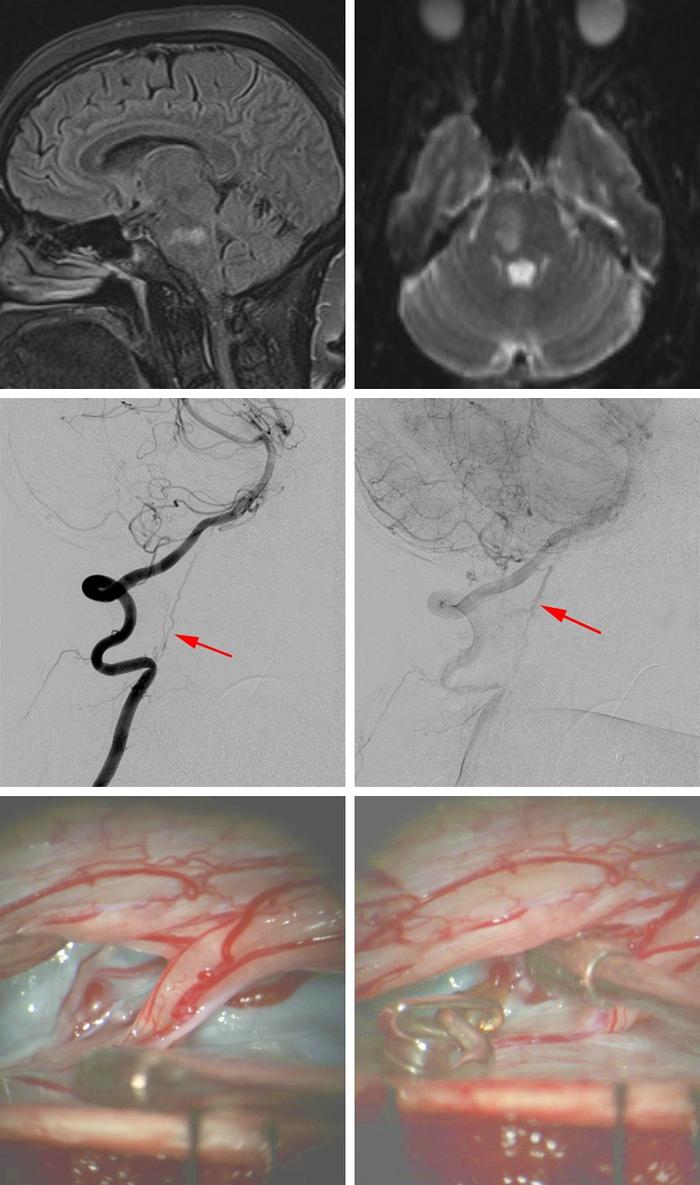

4:图中所示来自一名急性轻偏瘫和复视的54岁女性患者。磁共振显示右下桥脑缺血性梗死(最上排图)。头颈部血管造影显示颈部硬脊膜动静脉瘘。供血动脉起自椎动脉C3段,静脉沿颈髓和脑干表面向头端引流。给予患者行颈部椎板切开术和硬脊膜动静脉瘘断开术。术中发现三条起源于C2神经根前方的供血动脉予以电凝切断。切断引流静脉前先采用临时阻断夹阻断静脉,电生理监测脊髓无异常神经活动改变后,在背侧神经根入口水平予以切断。患者术后轻瘫症状明显好转。6个月后随访复查MRI已经显示缺血灶未进一步扩大。